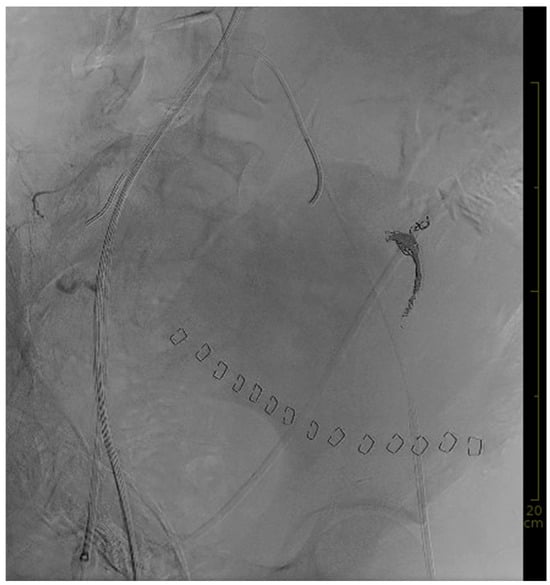

Upon arrival at the TCC, the patient was intubated, hypotensive at around 90 mmHg systolic pressure, and under continuous noradrenaline infusion at 0.15 µg/kg/min. In order to guarantee a multidisciplinary approach, the following specialties were present in the TCC upon arrival or had already been informed: obstetricians; emergency care physicians; anesthesiologists; and angiologists. Mass transfusion and advanced coagulation management, including viscoelastic testing and factor supplementation, was continued. Concurrently, a 7 French sheath was placed, under ultrasound guidance, into the right common femoral artery and a REBOA catheter (ER-REBOA® by Prytime Medical Inc., Boerne, TX, USA) was advanced into aortic zone III (infra-renal abdominal aorta). Less than five minutes after the decision was made to deploy a REBOA, the catheter was in place. Balloon placement was based on anatomical landmarks; the balloon was then inflated with 6 mL saline solution. After aortic occlusion, blood pressure increased, the heart rate decreased markedly, and noradrenaline was stopped within a minute. The patient was then transferred to the adjacent angiography room. The initial visualization of the bleeding is shown in Figure 1.

Figure 1. Initial angiography showing the extent of the bleeding with the REBOA in place.